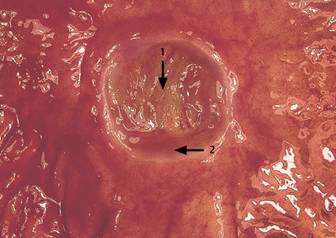

Ulcerul peptic

1. Baza ulcerului

2. Marginea ulcerului

Termenul de « ulcer peptic » include pe

langa ulcerul gastric « clasic », « tipic », si

ulcerele asociate cu stress-ul sau cu consunul de medicamente (aspirina si

alte AINS), si ulcerul asociat sindromului Zollinger - Ellison, determinat

de tumori secretante de gastrina localizate in pancreas sau duoden.